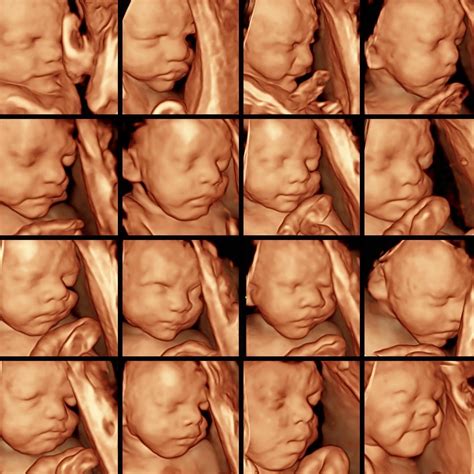

30 Week Ultrasound Image

Pregnancy is an exciting journey filled with milestones, and one of the most anticipated is the 30-week ultrasound. This scan is crucial for monitoring the baby's development and ensuring both the mother and the baby are healthy. Understanding what to expect during a 30-week ultrasound can help alleviate any anxieties and prepare you for this important check-up.

A 30-week ultrasound is a routine prenatal check-up that uses high-frequency sound waves to create images of the baby in the womb. This scan is typically performed between 28 and 32 weeks of pregnancy, with 30 weeks being a common timeframe. The primary goal of this ultrasound is to assess the baby's growth, development, and overall health.